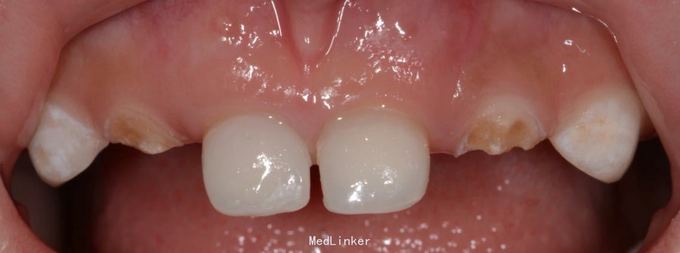

A1 B1残根,根尖炎。 常规根管治疗,树脂充填,抛光 A2 B2残根,常规去腐,备洞,树脂充填,抛光

乳牙功能恢复对发音,面部肌肉骨骼生长,儿童自信心的增长都有帮助